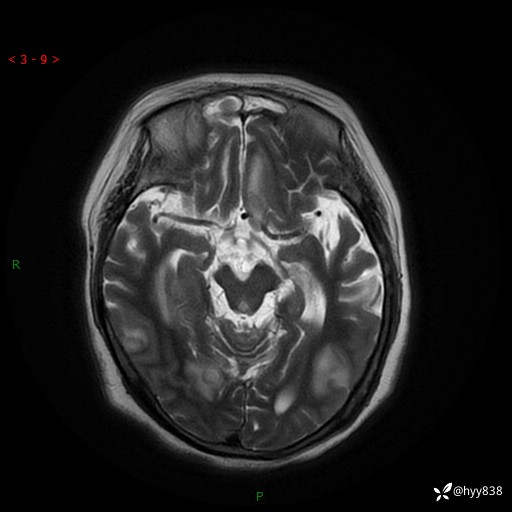

患者性别:女

患者年龄:57岁

简要病史:昏迷入院

临床诊断:昏迷

颅脑MRI(T2WI+DWI)